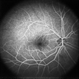

- Rinat Sutiushev, Ophthalmological center “Vision”, Saint Petersburg

- Imaging device

- Heidelberg Spectralis

- Fundus photograph of a 42-year-old man with retinal astrocytic hamartoma type 3.